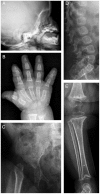

Recent advances in DNA sequencing have enabled mapping of genes for monogenic traits in families with small pedigrees and even in unrelated cases. We report the identification of disease-causing mutations in a rare, severe, skeletal dysplasia, studying a family of two healthy unrelated parents and two affected children using whole-exome sequencing. The two affected daughters have clinical and radiographic features suggestive of anauxetic dysplasia (OMIM 607095), a rare form of dwarfism caused by mutations of RMRP. However, mutations of RMRP were excluded in this family by direct sequencing. Our studies identified two novel compound heterozygous loss-of-function mutations in POP1, which encodes a core component of the RNase mitochondrial RNA processing (RNase MRP) complex that directly interacts with the RMRP RNA domains that are affected in anauxetic dysplasia VSports手机版. We demonstrate that these mutations impair the integrity and activity of this complex and that they impair cell proliferation, providing likely molecular and cellular mechanisms by which POP1 mutations cause this severe skeletal dysplasia. .